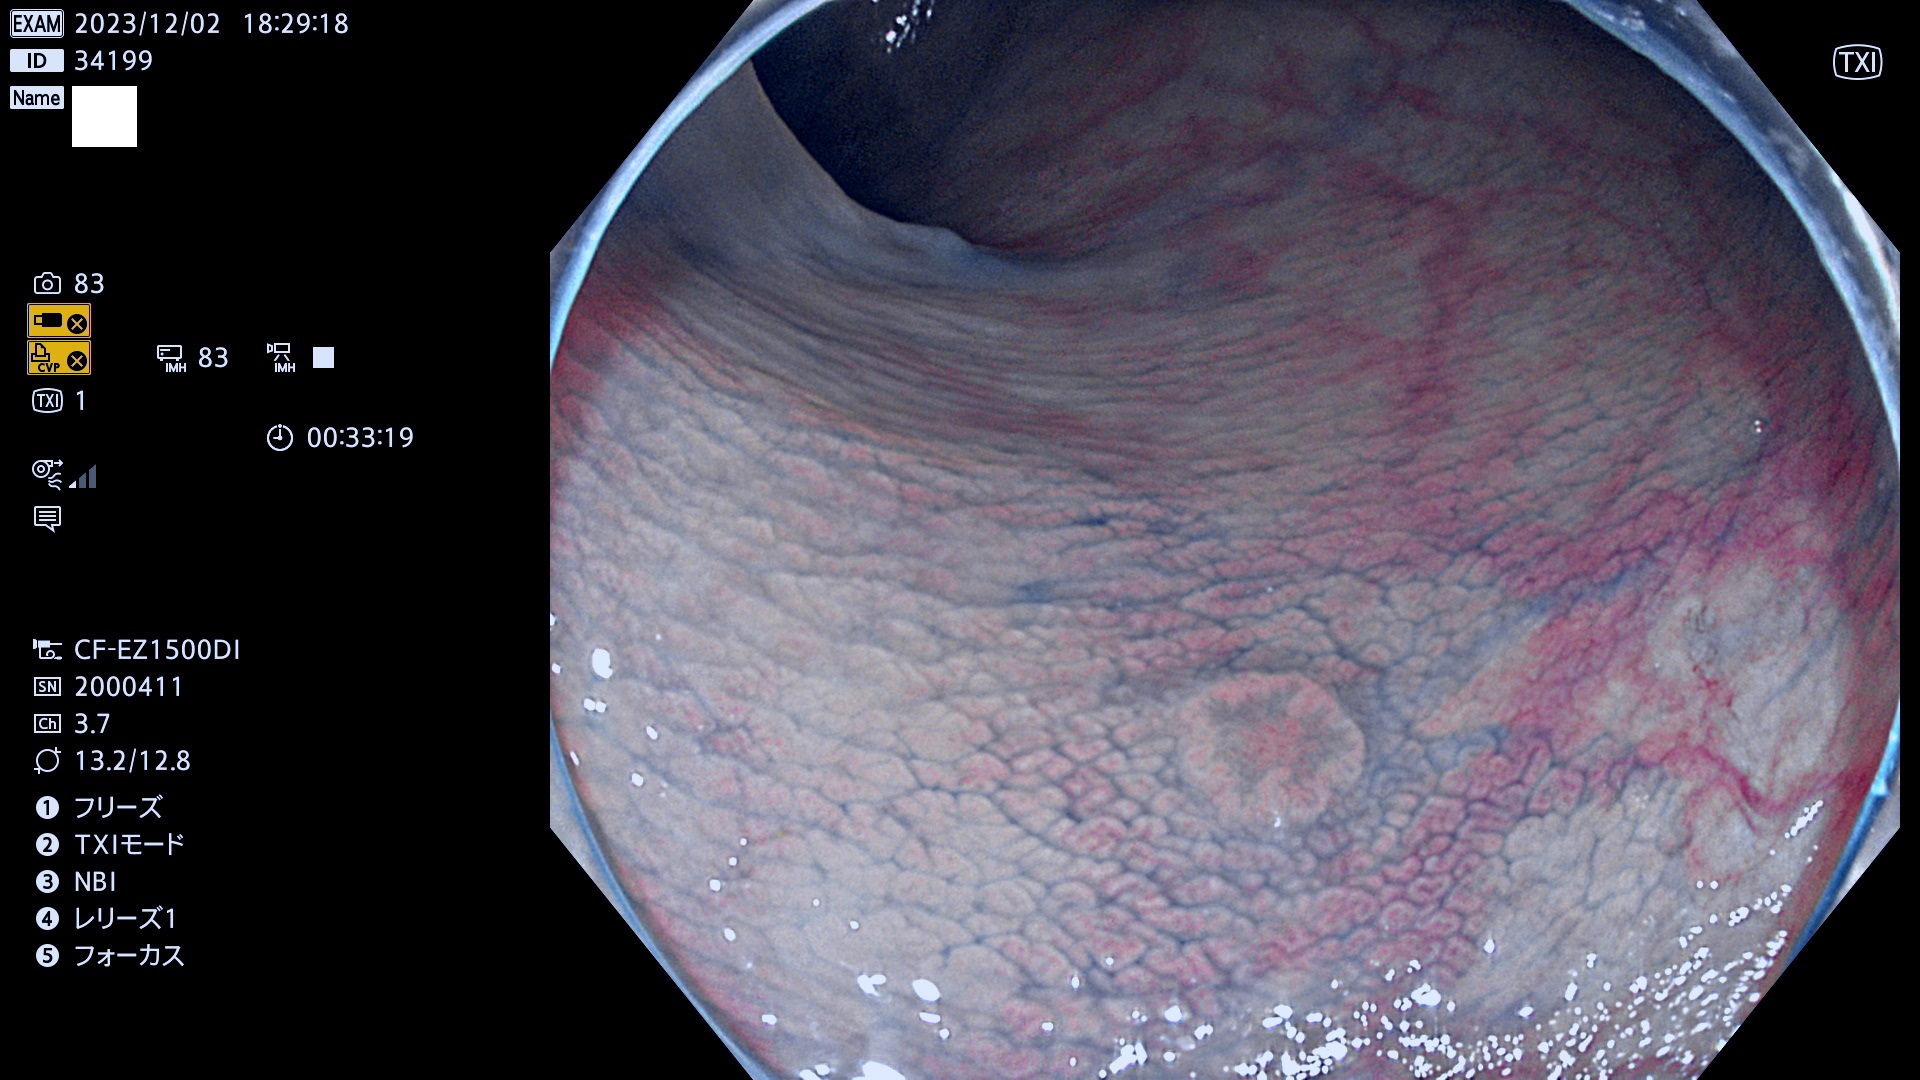

表面型腺腫(Flat Adenoma)の中で、完全に平坦な物をUb、陥凹している物をUcと呼びます。平坦隆起型(Ua)よりも、発見が難しく危険な病変です。このタイプは「内視鏡後・大腸癌の重要犯人」であり、この発見率は「腺腫発見率」よりも、重要な意味があります。

毎週の検査(木・金・土・日)に発見されたUb、Uc型・腺腫を、その週の日曜の夜にUPし1週間、提示します。

抽出の対象期間 2023年11月30日(木)〜12月4(月)の5日間(60件の検査)6件